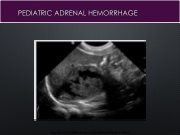

Page 23 - ADRENAL GLAND sono 260